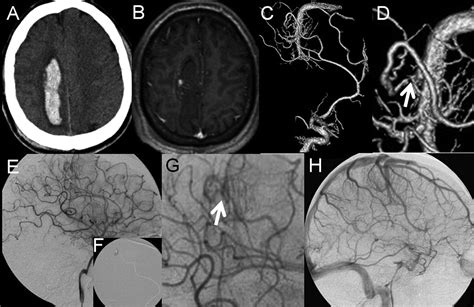

While DVAs are generally considered benign, they can sometimes be associated with other vascular malformations, such as cavernous malformations or arteriovenous malformations (AVMs). These associations can complicate the clinical picture and may require more aggressive management strategies.

• Intracranial hemorrhage

Diagnosing a DVA typically involves imaging studies, such as magnetic resonance imaging (MRI) or computed tomography (CT) scans. These imaging techniques can reveal the characteristic appearance of DVAs, which include:

In some cases, additional imaging studies, such as angiography, may be performed to better visualize the venous drainage patterns and rule out other vascular malformations.

• Endovascular treatment: Minimally invasive procedures, such as embolization, may be used to occlude the abnormal venous channels and reduce the risk of complications.